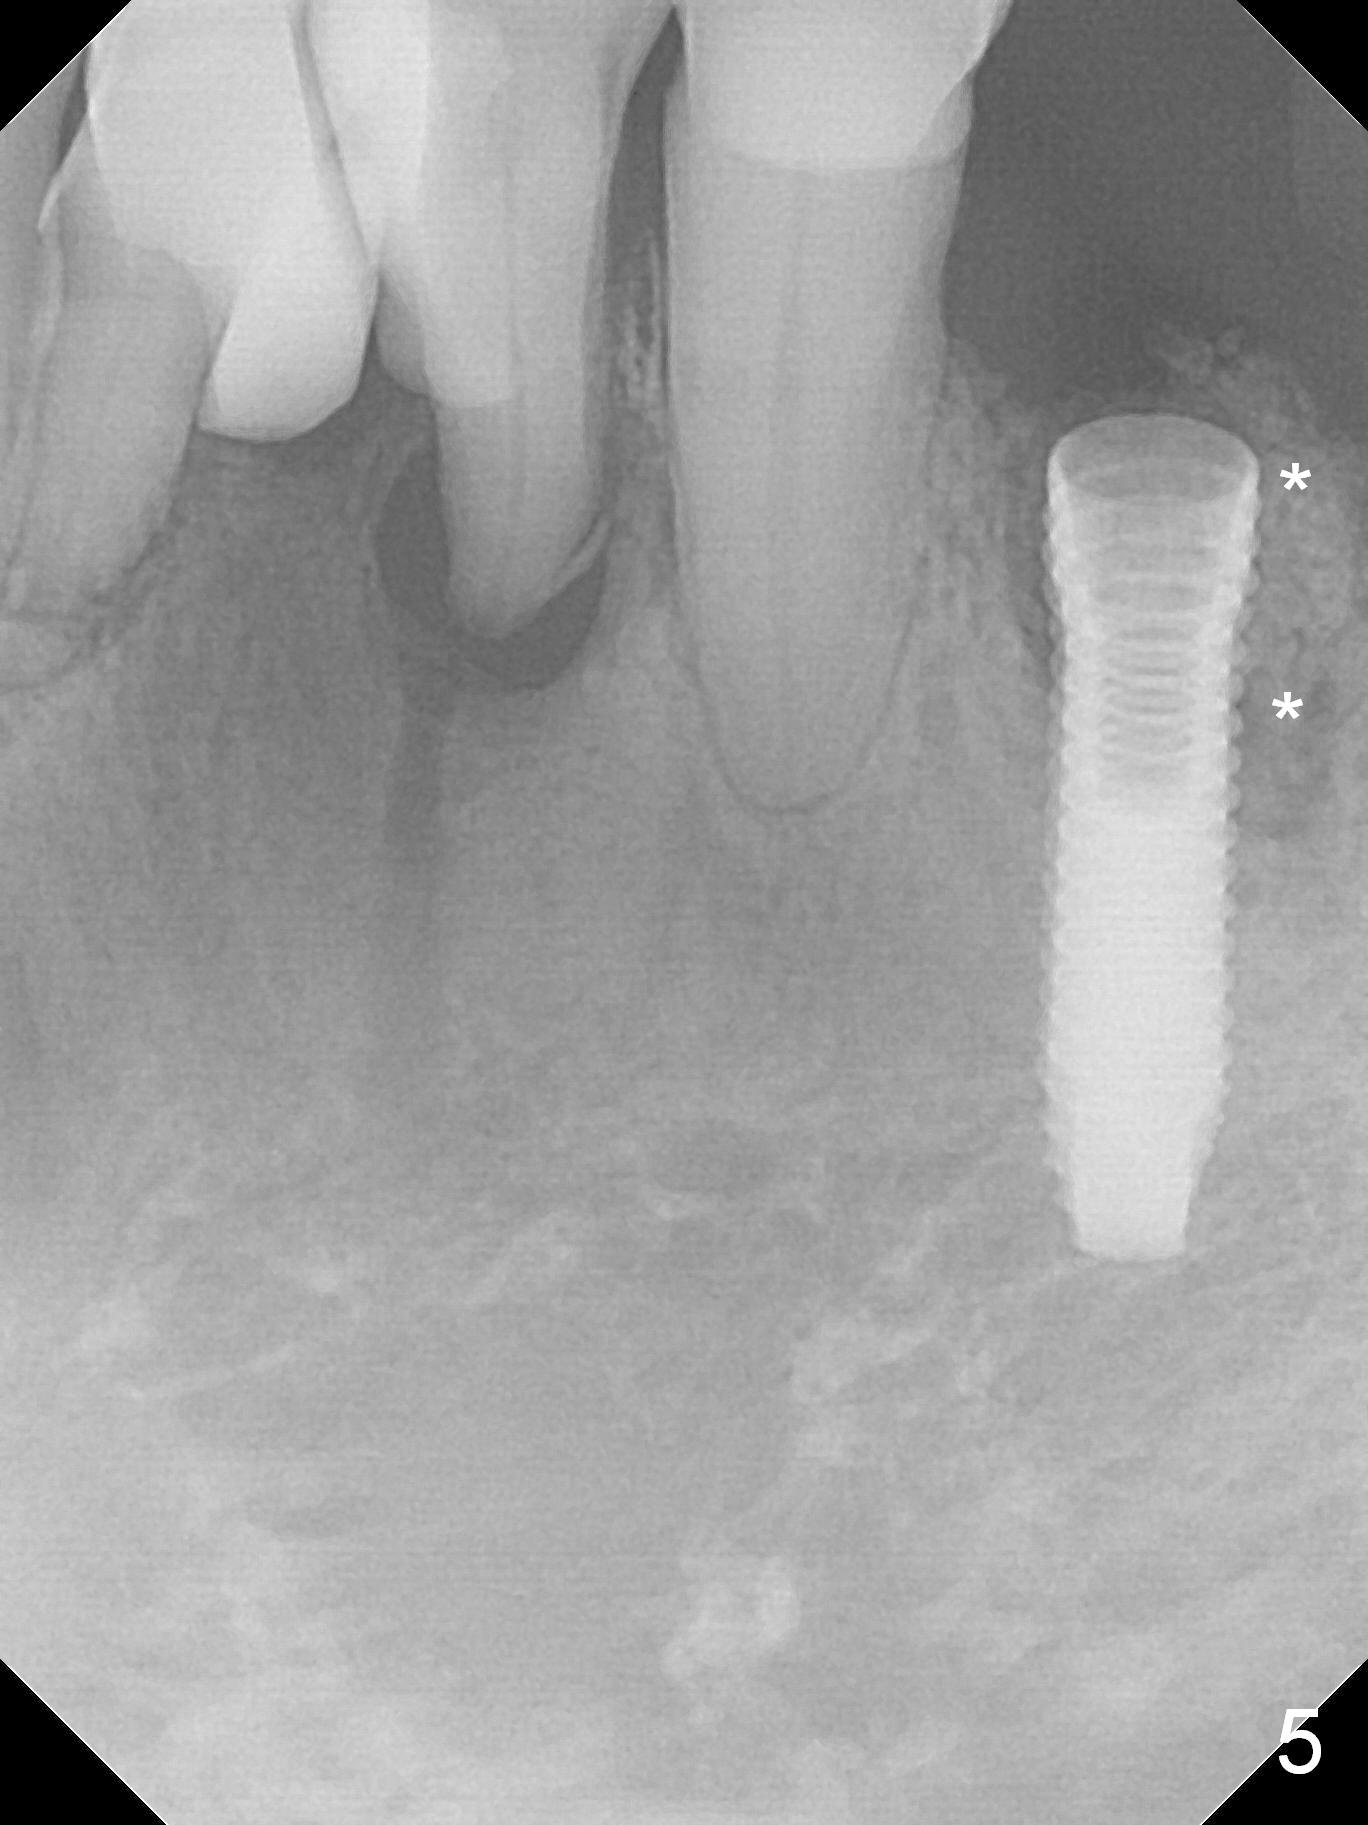

A 72-year-old man presents to clinic for implants because of pain associated with wearing the lower partial. The teeth #21, 24, 25 and 31 seem to be non-salvageable and are going to be replaced by implants so that the lower RPD can be reused (Fig.1). The edentulous ridge is atrophic (Fig.9 *). The upper complete denture appears to be functional. Since the tooth #21 is symptomatic (Fig.2) and the patient has chronic TMJ dislocation, the affected tooth is extracted first (Without antibiotic socket treatment) for immediate implant (Fig.3 (1.5 mm drill (placed more lingually)). The lower RPD is used as a surgical guide (Fig.4 (3 mm drill in place)). When a 3.8x16 mm implant is placed with bone graft (Fig.5 *), the underlying neurovascular bundle is undetected. A small field of panoramic X-ray is retaken; it seems that there is enough clearance from the Mental Foramen (Fig.2,6,7 (red dashed line)) and the Incisive Canal (pink dashed line). The implant is then placed 2 mm more apically (Fig.7) to reduce the chance of periimplantitis since the buccal plate is lost. A 5.5x5(5) mm abutment is placed (Fig.5) with more graft. The access of the abutment is left open so that a part of periodontal dressing is inserted for additional retention (Fig.8,9). The RPD is placed back for adaptation of the dressing. The patient is advised not to wear the RPD postop to reduce micromovement.

The patient returns 2 days postop because of hemorrhage (Fig.10,11 * after removal of loose periodontal dressing). Periodontal dressing is repacked (Fig.12). The hemorrhage may be due to incomplete removal of granulation tissue or invasion of the Incisive vessel intraoperatively, although there is no pain or paresthesia postop. Soft food is recommended without the upper complete denture. A provisional is fabricated (Fig.14 P) nearly 3 months postop (after changing the 5.5x5(5) mm abutment to 4.5x5(4) mm, Fig.13) when an implant is being place is #31.